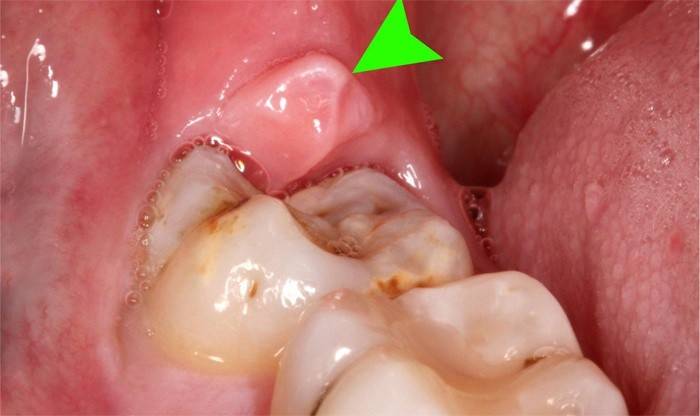

El proceso inflamatorio con el crecimiento de los ochos aparece porque, debido a la erupción lenta, parte del molar permanece cubierto con una membrana mucosa, una capucha durante mucho tiempo. Este tejido contiene piezas de alimentos que son difíciles de eliminar durante la limpieza higiénica de la cavidad oral, lo que provoca el crecimiento de gérmenes y, como resultado, inflamación de las encías alrededor de la muela del juicio. Un método efectivo para tratar este problema es la escisión de la capucha, una simple manipulación dental, que en unos minutos eliminará el riesgo de posibles complicaciones: hinchazón de los tejidos blandos, supuración.